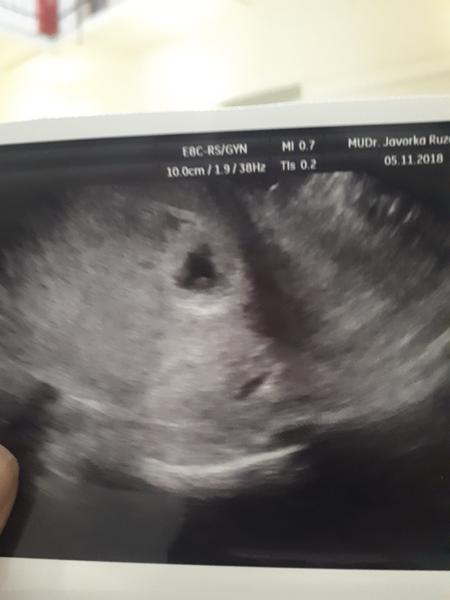

@veronikaszabova hej to je s pred roka ja som len chcela ukázať že to čo tam videl bolo niečo takéto